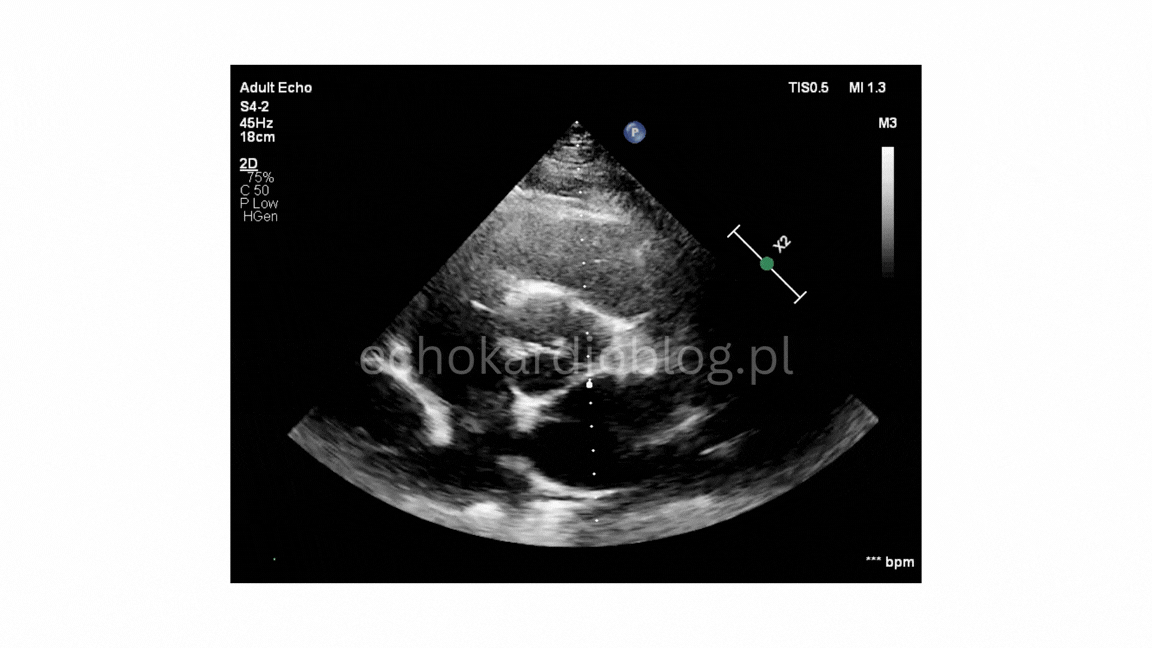

Przypadek 1.A

W pierwszym filmie obraz jest doskonały i budowa zastawki jest oczywista. W drugim – rozpoznanie wymaga większej uwagi i doświadczenia.

In the first video, the image quality is excellent, and the bicuspid morphology is obvious. In the second one, the diagnosis requires more attention and experience.